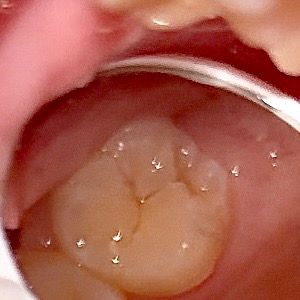

심각한 충치나 치수염 가능성이 있어보이나요??

심각한 충치나 치수염 가능성이 있어보이나요?? 치통인지 아님 생리전증후군인지.. 이쪽 부근에 은은한 통증? 불쾌감이 느껴져서요ㅜㅜ

• 2번 째 사진

치아 파절이 관찰되는데 파절 주위로 크랙이 의심됩니다 충치나 치수염이 아니더라도 크랙으로 통증이 심할 수 있습니다

이정도면 범랑질에 국한된 충치 입니다. 사진이 흐리지만 표면충치로 보이며 당분간 치료 안하고 그냥 지켜보다가 혹시 더 진행되면 충치치료 해도 될 것으로 보입니다.

사진 상으로는 단순 히 착색이 된 정도로 보이며 치수염이나 심한 충치가 의심되진 않습니다.

사진상으로 심각한 충치같이 보이거나 그렇진 않습니다. 간단한 충치치료를하면될것같습니다.